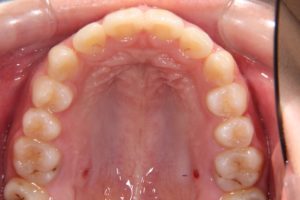

下顎の重度叢生ケースです。

治療前

銀歯は乳歯です。叢生が多いと歯磨きも大変です。歯石もつきやすいです。

治療後

重なっていた下の前歯も綺麗になりました。

口元も治療後の方が閉じやすくなっています。叢生を治して口も閉じやすく!

E-ラインを考慮した非抜歯での治療が重要です。